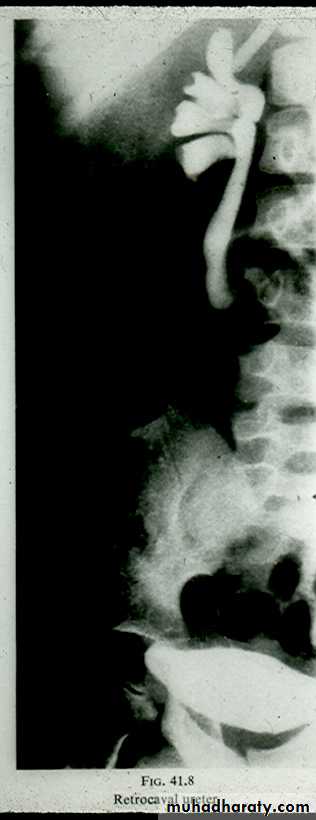

Retro- caval ureter :

* Rare .

* The middle third of right ureter curve medially behind the IVC , then laterally to regain it’s normal position , this lead to obstruction of upper third of ureter .

Congenital anomalies of ureter